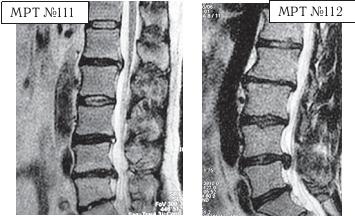

Вот ещё случаи послеоперационных рецидивов грыж — естественной реакции организма, когда проблема решается однобоко — всего лишь с помощью хирургической операции в поражённом сегменте без общего восстановления биомеханики позвоночника.

На МРТ № 111 поясничного отдела позвоночника отмечается рецидив — грыжа межпозвонкового диска LIV-LV после трёх операций. Даже если прооперировать в четвёртый раз, то это всё равно не решит проблемы и не добавит здоровья данному пациенту, так как неизбежно возникнут осложнения в вышележащих сегментах LI—LII LIII—LIV в силу биомеханических нарушений в позвоночнике и выраженных дегенеративно-дистрофических изменений в указанных сегментах.

На МРТ № 112 поясничного отдела позвоночника отмечается рецидив — секвестрированная грыжа межпозвонкового диска в сегменте LIV-LV после четырёх операций. Здесь, как говорится, без комментариев.